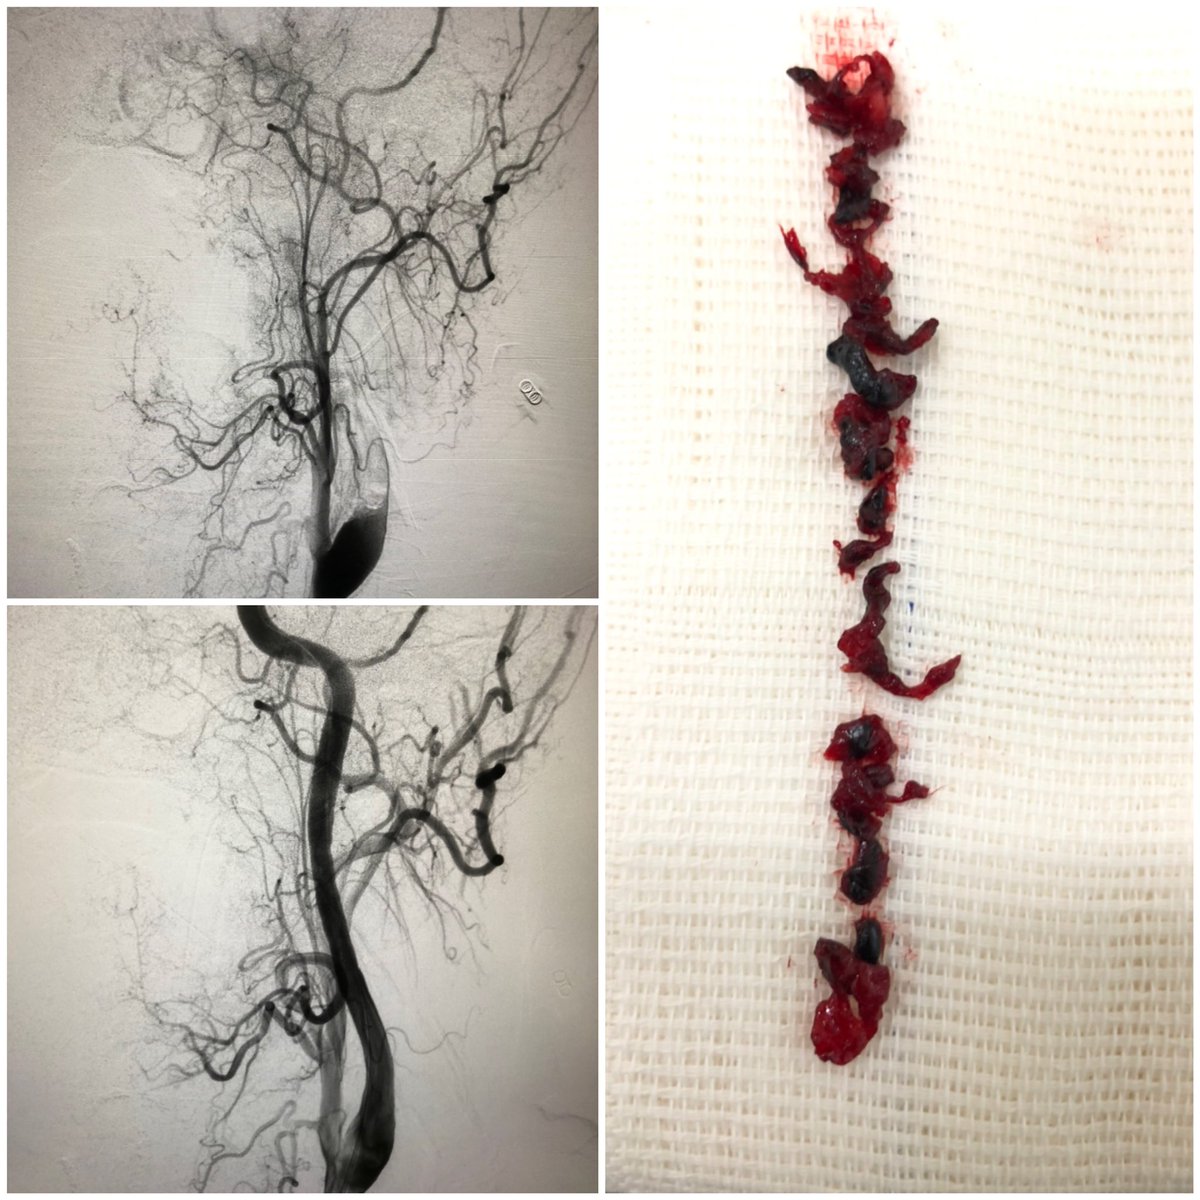

Today’s thrombectomy shows the role of direct manual aspiration through balloon guide catheter for carotid large clot burden. #stroke #largeclot #thrombectomy